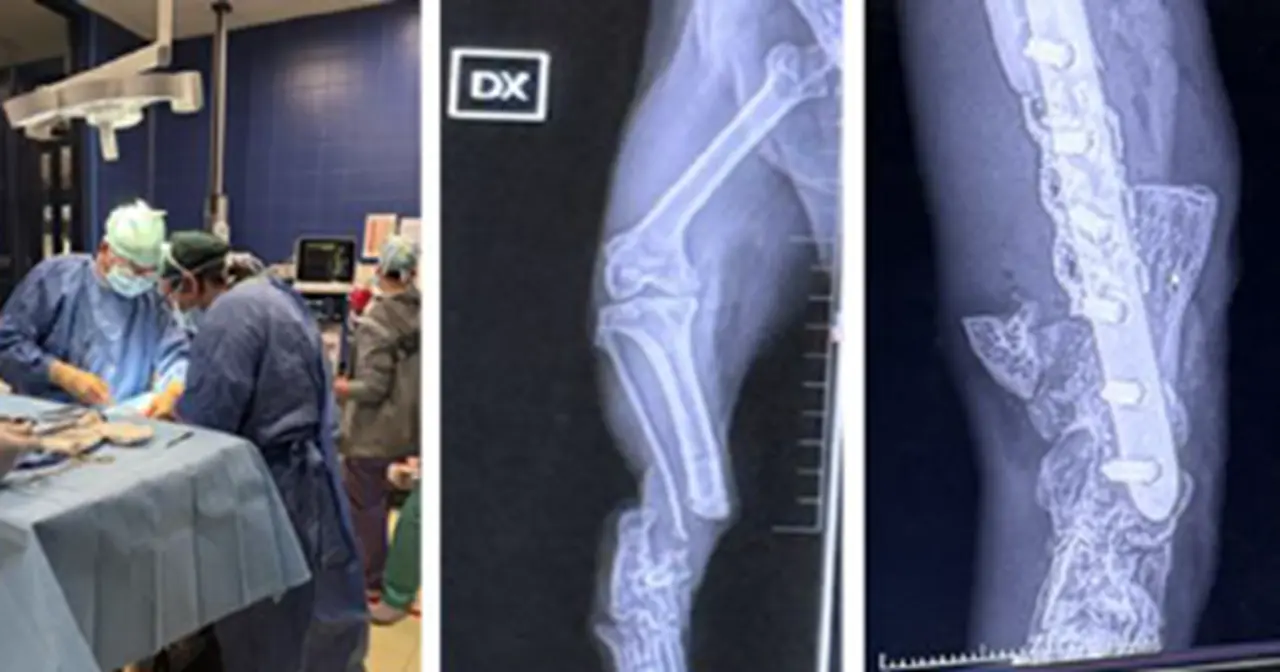

Kërkimi shkencor në Universitetin Bujqësor të Tiranës, nëpërmjet bashkëpunimit midis Universitetit të Barit “Aldo Moro”, Departamenti i Mjekësisë Precize dhe Regjenerative dhe i Zonës Joniane – DIMEPRE-J, përmes programit të Doktoraturave të përbashkëta, ka arritur që të bëjë hulumtime shkencore në fushën e terapisë së indeve të buta. Kjo metodë inovative e aplikueshme sot në qasjen "Një Shëndet" ka për synim rigjenerimin e indeve të buta në njerëz dhe në kafshë nëpërmjet metodave inovative të nxitjes së krijimit të qelizave staminale, për rigjenerimin e indeve të dëmtuara në mënyrë të pakthyeshme.

Kjo metodologji synon të aplikohet si në mjekësi veterinare ashtu edhe në mjekësi humane nëpërmjet ekselencës shkencore të Departamentit të Mjekësisë Precize dhe Regjenerative dhe të Zonës Joniane – DIMEPRE-J, për rigjenerimin e indeve të tendinave të muskujve, të neuroneve, të fijeve nervore, si edhe të qelizave të miokardit.

Ky projekt kaq ambicioz e vizionar, në drejtim të dhënies së zgjidhjeve që deri tani kanë qenë kaq sfiduese, siç janë rigjenerimi i indit nervor, ka dhënë rezutate fillestare shumë të suksesshme, të cilat vërtetojnë se shumë shpejt këto do të jenë të aplikueshme edhe në njerëz.

Edhe njëherë shumë mirënjohje dhe vlerësim për profesor Antonio Crovace, Departamenti i Mjekësisë Precize dhe Regjenerative dhe i Zonës Joniane – DIMEPRE-J. Po ashtu falenderime për kontributin dhe angazhimin maksimal të doktorantëve Bledar Goxhaj dhe Taulant Goga, të cilët me shumë sukses po përfundojnë doktoraturat e tyre në këtë fushë, nën udhëheqjen e përbashket të Prof. Dr. Erinda Lika, Zv.Rektore për Shkencën dhe Projektet në UBT dhe profesor Antonio Crovace.